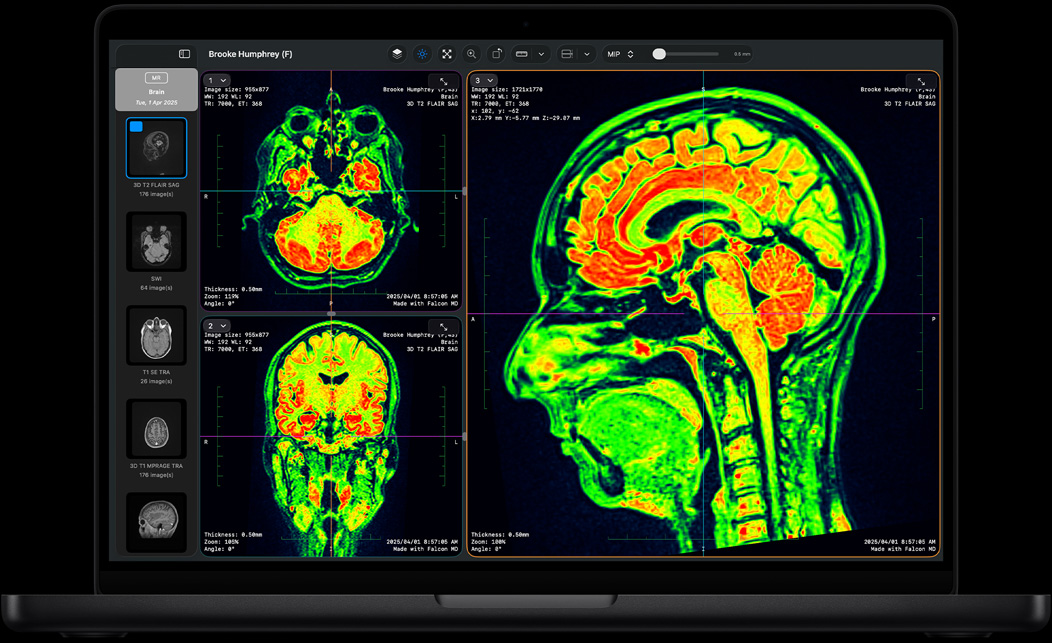

M4 Pro 实力更为强悍,可满足用户的更高需求,从数据库设计、数据建模到 DNA 测序,全面提速。无论选择 14 英寸还是 16 英寸机型,搭载 M4 Pro 的 MacBook Pro 都能轻松处理繁重任务,其出色的图形性能还让 3D 渲染和动画处理快上加快。

Falcon MD